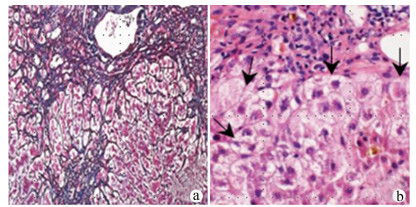

A case of primary carcinosarcoma of the liver

Wei YU, Chengbin ZHANG, Yan MA

2021, 37(12): 2890-2890. DOI: 10.3969/j.issn.1001-5256.2021.12.030

Abstract(760) HTML (212) PDF (3011KB)(72)

Abstract: